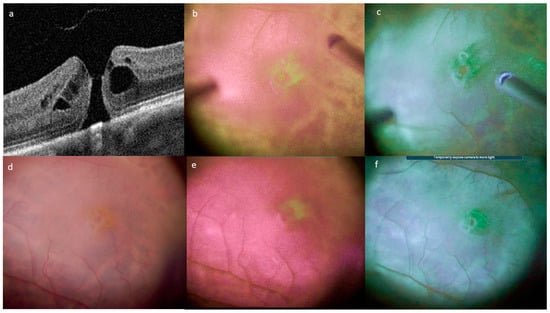

Tissue Color Modifications